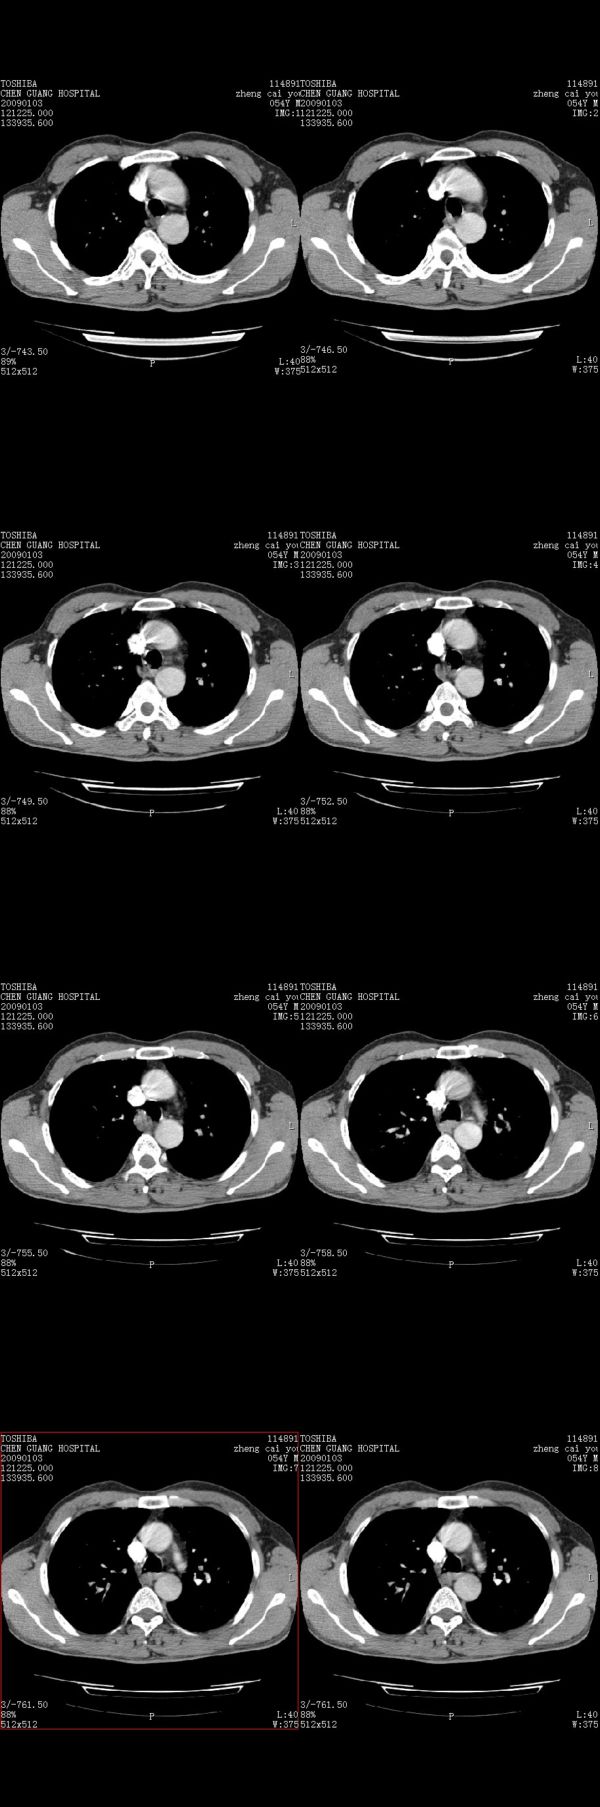

男,54岁,右侧胸部疼痛,平时吸烟,有抽烟后咳嗽咯痰史。昨天没把xiphoid软件吃懂,所以没把纵隔窗图像处理出来!请各位老师帮忙看一下右肺门有没有问题?谢谢!!!!!!!!!!

右肺上叶后段近气管旁仍可见一结节灶,不除外为肿大的淋巴结影。

气管前腔静脉后似见增大淋巴结影,肺门区未见明显肿块影。肺窗示右肺中叶外侧段透亮度增高,可过一段时间再查一下对比一下,毕竟是自己的至亲,又有条件,辐射就顾不得了。

也觉得还好吧,只是右下肺动脉显粗了点,纵膈有钙化淋巴结,再有肺窗就更好了

各位老师:奇静脉增宽,肺上未见明显实变,这还需注意观察些什么?????

右侧肺门影增大,不除外增大淋巴结可能

上腔静脉后淋巴结影,不知道最后结果怎么样?